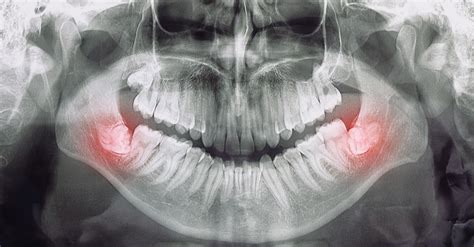

No siempre es necesario realizar la extracción de las muelas del juicio cuando te empiezan a salir, pero es un procedimiento bastante habitual. Para muchas personas, surgen con normalidad y no causan ningún problema. Sin embargo, si una muela del juicio no tiene espacio para crecer (muela del juicio impactada), lo que provoca dolor, infección u otros problemas dentales, es probable que necesite ser extraída. Para prevenir posibles problemas futuros, los odontólogos pueden recomendar la extracción de las muelas del juicio incluso cuando la muela no esté causando problemas actualmente.

La falta de espacio para el crecimiento adecuado de las muelas del juicio puede generar diversos problemas, como dolor, infecciones, quistes, daño a los dientes adyacentes y maloclusiones. Además, su ubicación en la parte posterior de la boca dificulta el acceso para una correcta higiene dental, lo que aumenta el riesgo de caries y enfermedad periodontal.

Cuando las muelas del juicio no logran erupcionar completamente o lo hacen de forma parcial y en una posición inadecuada, se les denomina “muelas del juicio impactadas” o “incluidas”. Es importante mencionar que no todas las personas desarrollan las cuatro muelas del juicio, y en algunos casos, es posible que no aparezcan en absoluto.